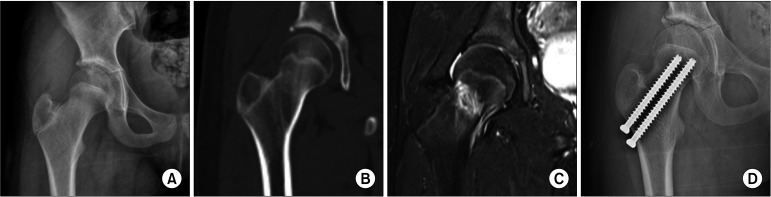

Results: Excluding 2 patients lost to follow-up, 4 of 13 patients (30.77%) in the low-energy fracture group were underweight, whereas none in the high-energy fracture group were underweight. Including valgus impacted femoral neck fractures, 7 femoral neck fractures were nondisplaced, while 13 were complicated with displacement and required closed reduction. Avascular necrosis was observed in 4 cases and limb length discrepancy in 3 cases. The mean BMI percentile differed statistically significantly between the 2 trauma groups (p < 0.05).